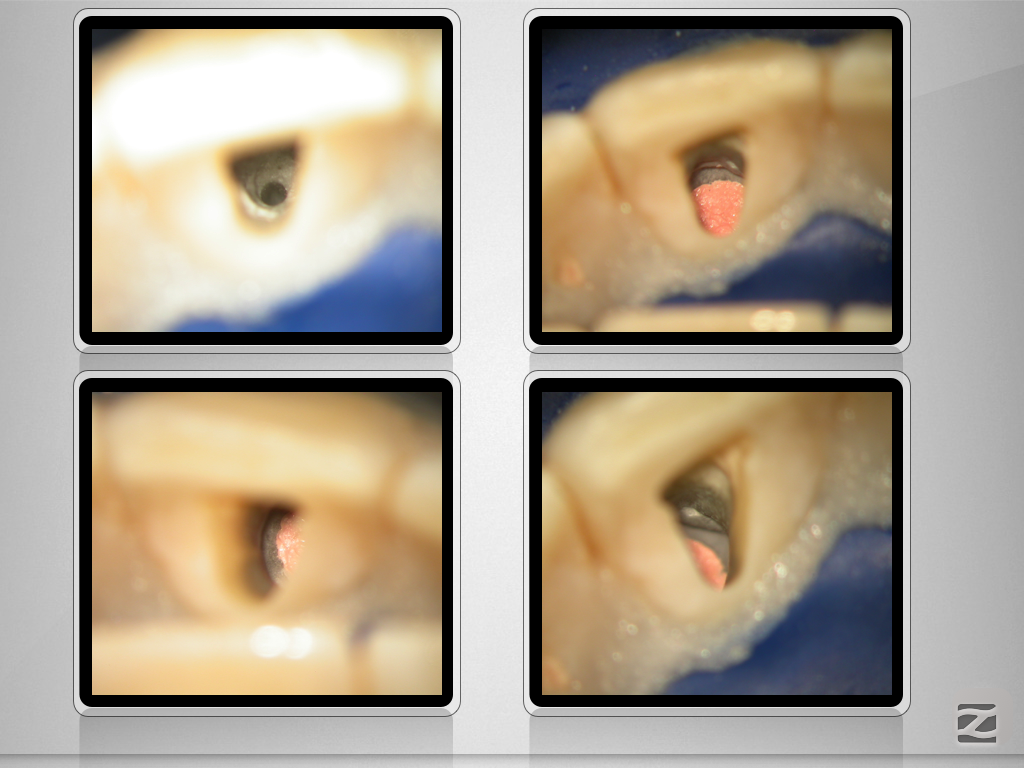

Wie eine Pulpanekrose einen Zahn retten kann.